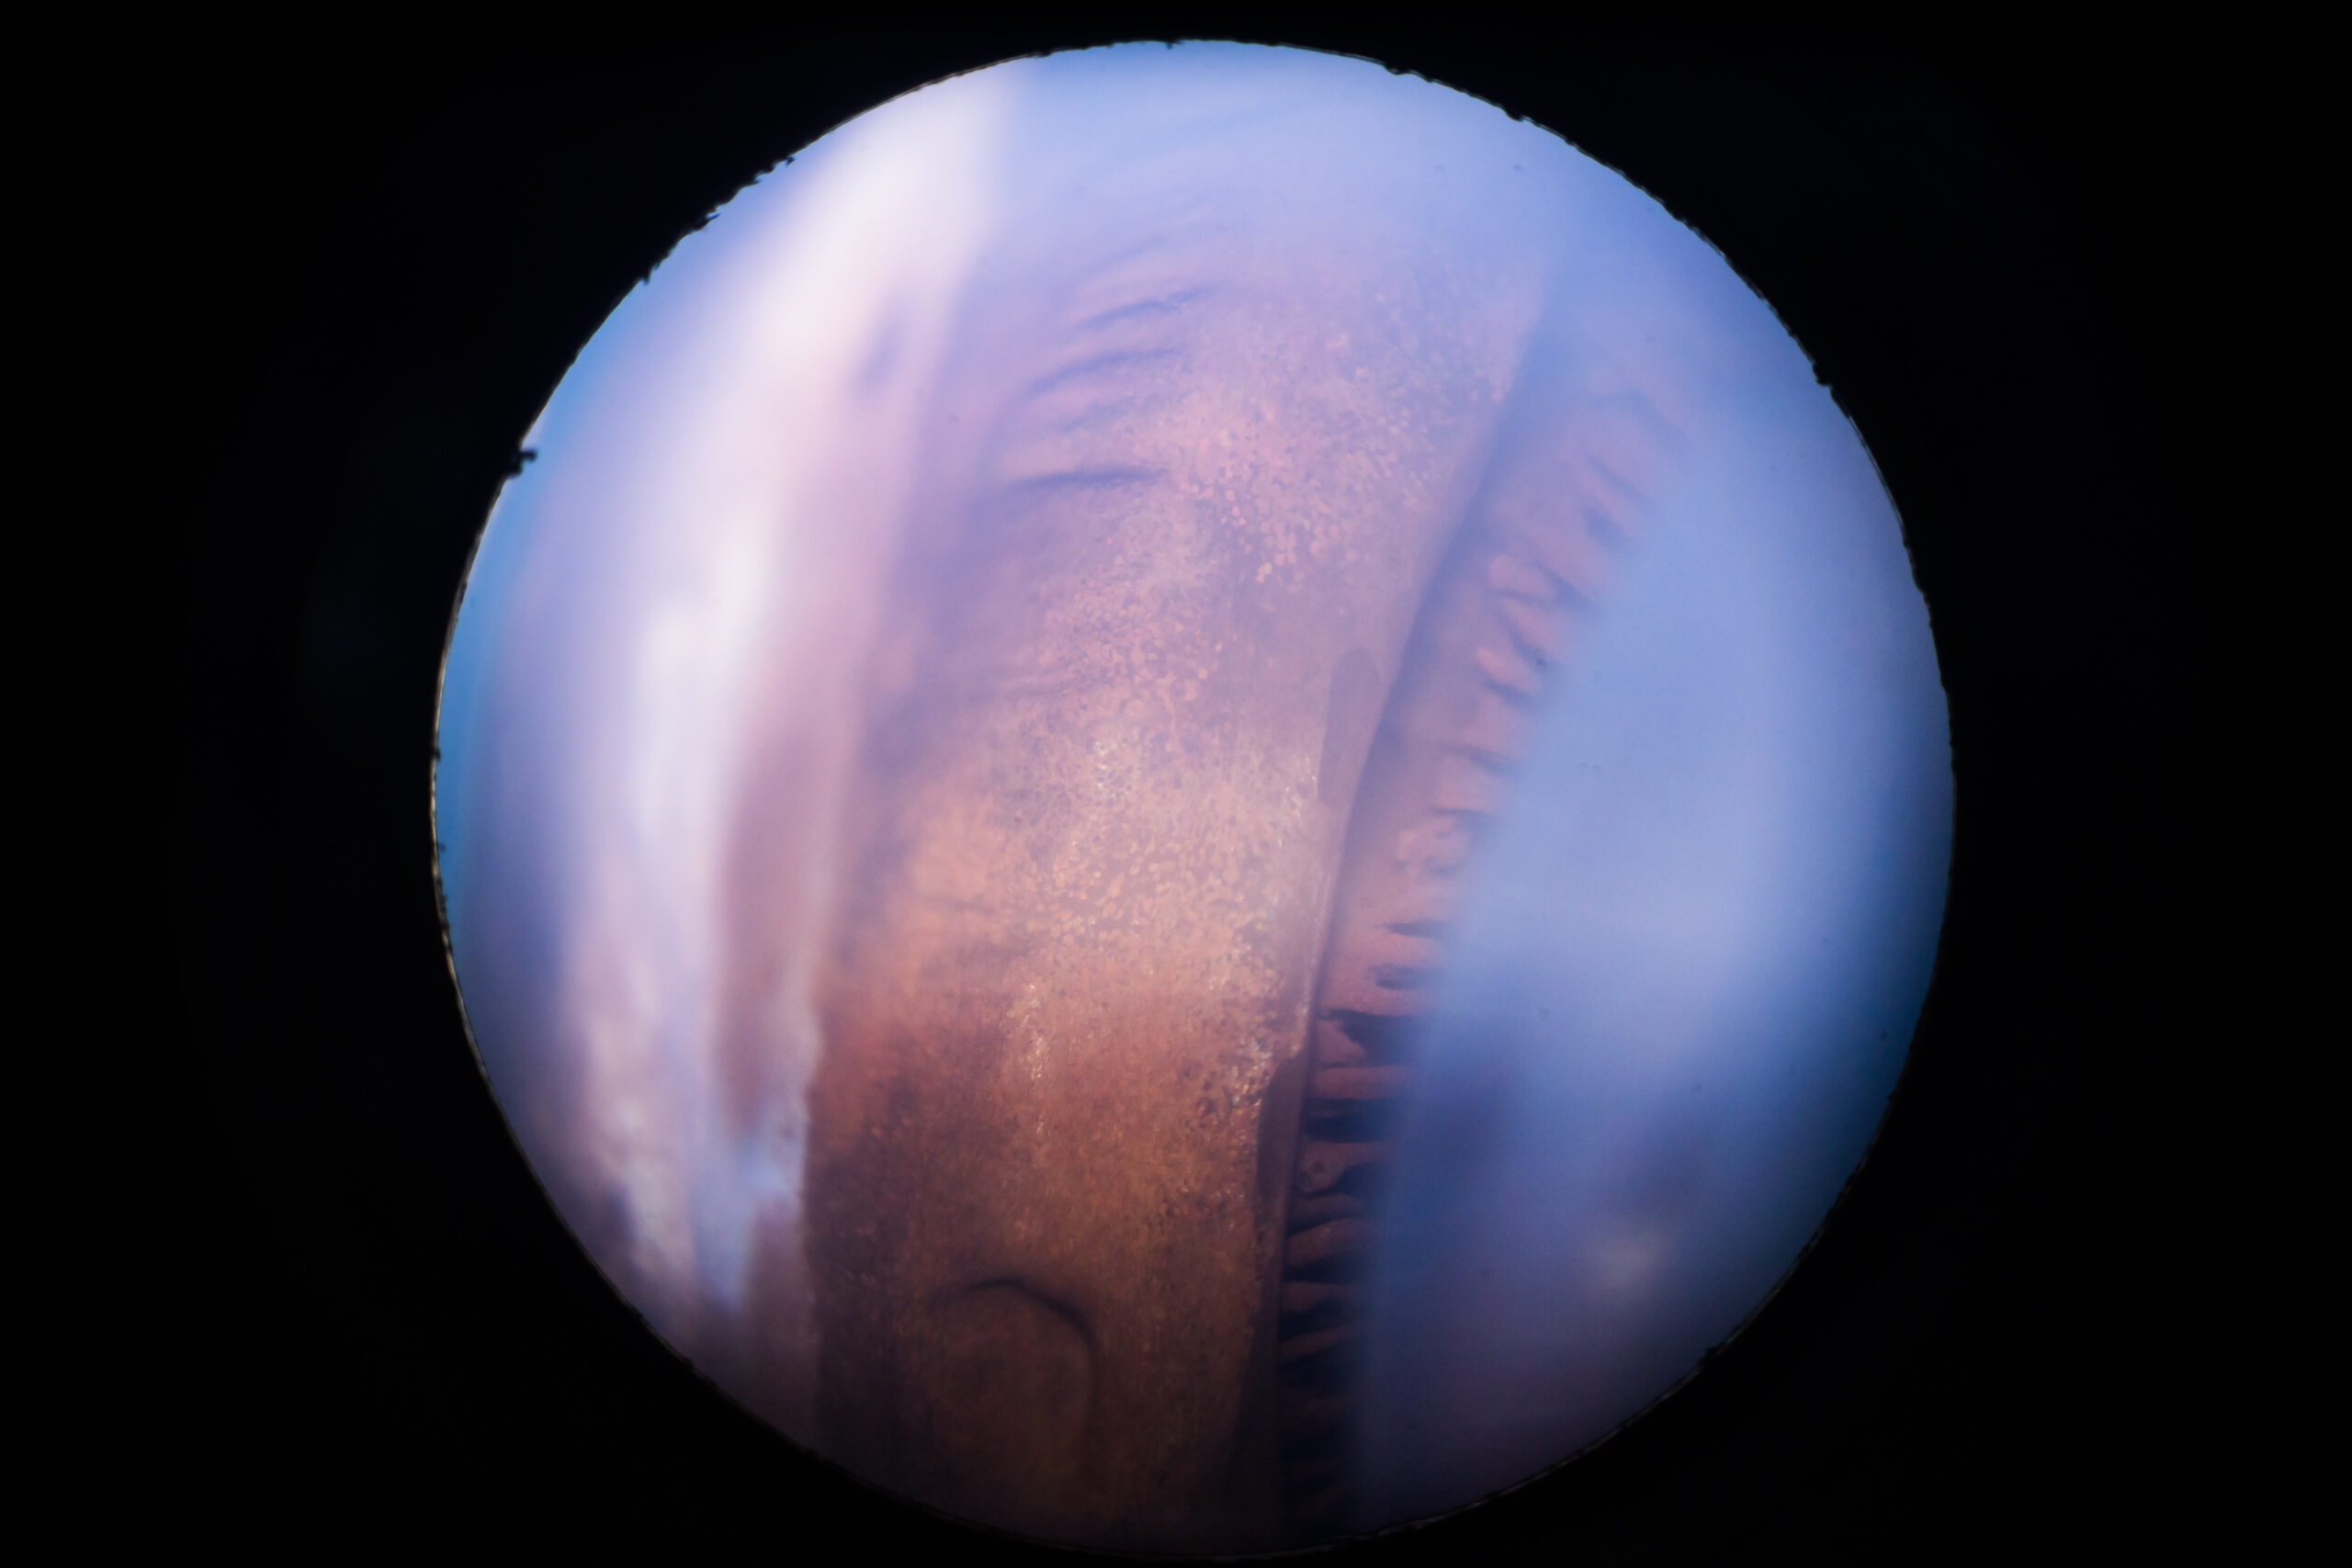

Un chien Cairn Terrier femelle de 10 ans a été présentée en consultation pour l’évaluation d’un glaucome évoluant depuis quelques semaines et ne répondant pas au traitement médical prescrit jusqu’alors (association d’un bétabloquant et d’un inhibiteur de l’anhydrase carbonique par voie locale). A l’examen, la vision a été considérée comme abolie avec absence de réponse à la menace et à l’éblouissement du côté droit. Les photographies 2a et 2b montrent l’aspect de l’œil au moment de la consultation. La photographie 2c est une vue gonioscopique de l’angle iridocornéen à travers une lentille de Koeppe de 17mm.

La pupille est dilatée et ne se contracte pas à la lumière, à tel point qu’il n’est pas visible sur la photographie. Des foyers pigmentés sont visibles sur la capsule antérieure du cristallin. La vue latérale montre un envahissement de la sclère par du pigment. La vue gonioscopique confirme la forte dilatation de la pupille. Les structures qui composent habituellement l’angle iridocornéen sont complètement désorganisées. Le ligament pectiné n’est plus visible et la fente ciliaire a été progressivement comblée par du pigment. Les procès ciliaires sont aussi épaissis et recouverts de pigment.